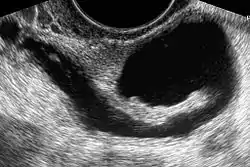

La histerosonosalpingografía, se trata de una ecografía del útero y de las trompas.[1]

Procedimiento

Principalmente, las imágenes ecográficas obtenidas por la histerosonosalpingografía pueden mostrar anomalías uterinas o de las trompas de falopio, tanto desde un punto de vista morfológico como fisiológico.[5]